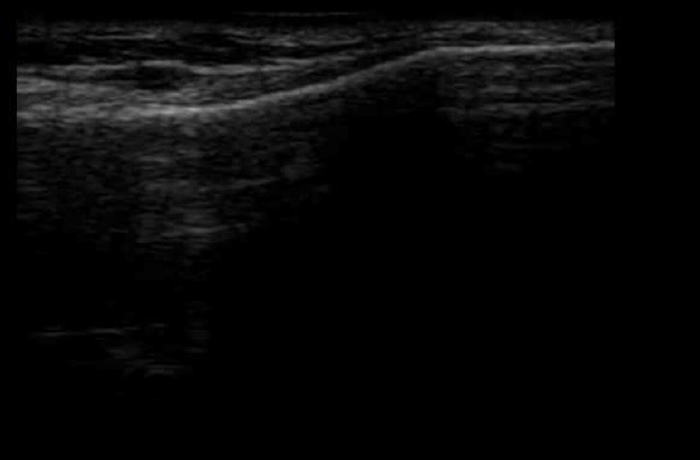

③ あまり伸びない時期

この時期は、骨端線がほとんど閉鎖しており、隙間がわずか、または完全に閉じている状態です。

この段階になると、骨の成長はほぼ完了しており、身長が大きく伸びることはほとんどありません。大人と同じように骨端線が確認できなくなることもあります。